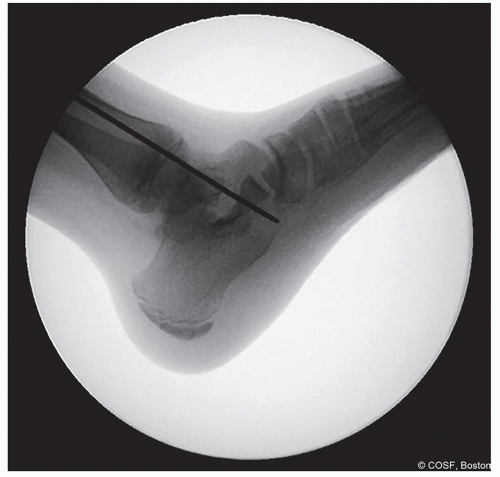

Figure 28-7 ▪ Guide pin entry into the calcaneus—proper position. (Courtesy of Children’s Orthopaedic Surgery Foundation.)

Figure 28-8 ▪ Lateral view fluoroscopy showing the guide pin in the proper location. (Courtesy of Children’s Orthopaedic Surgery Foundation.)